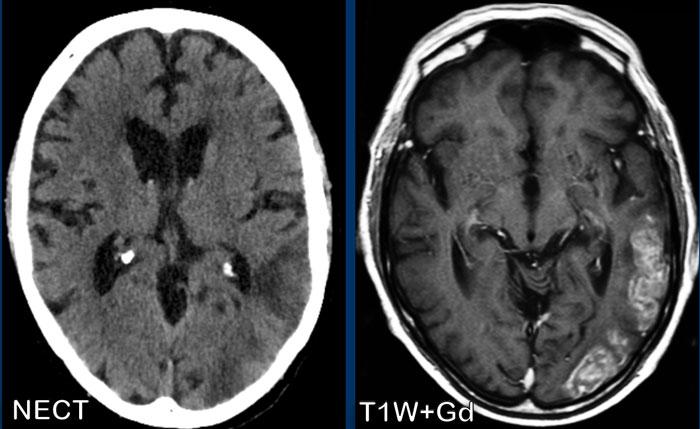

U lympho

Các hình ảnh này của một phụ nữ 76 tuổi, có biểu hiện lú lẫn sau khi ngã.

Các dấu hiệu bao gồm:

- Tổn thương tăng tỷ trọng trên CT không tiêm thuốc cản quang kèm phù não do mạch máu.

- MRI cho thấy nhiều tổn thương ngấm thuốc dạng đặc và hạn chế khuếch tán.

- Trên chuỗi xung T2W, các tổn thương biểu hiện giảm tín hiệu.

- Một tổn thương nằm ở thể chai và một tổn thương khác nằm cạnh não thất.

Tất cả các dấu hiệu này đều điển hình cho u lympho nguyên phát hệ thần kinh trung ương, khác với u lympho hệ thống.

Các khối u này chiếm 6-7% tổng số u hệ thần kinh trung ương và mô học là u lympho tế bào B không Hodgkin.

Chúng thường nằm ở vùng cạnh não thất dưới màng nội tủy, thể chai và hạch nền.

Luôn nghĩ đến u lympho khi gặp tổn thương ngấm thuốc dạng đặc nằm gần não thất.

Hình ảnh tăng tỷ trọng trên CT, giảm tín hiệu nhẹ trên chuỗi xung T2W cũng như hạn chế khuếch tán được giải thích là do mật độ tế bào dày đặc của mô u lympho.